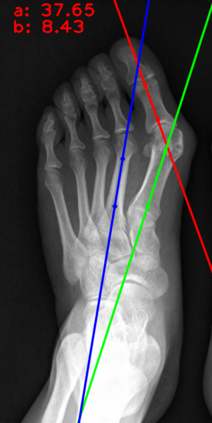

Angular measurements is essential to make a resonable treatment for Hallux valgus (HV), a common forefoot deformity. However, it still depends on manual labeling and measurement, which is time-consuming and sometimes unreliable. Automating this process is a thing of concern. However, it lack of dataset and the keypoints based method which made a great success in pose estimation is not suitable for this field.To solve the problems, we made a dataset and developed an algorithm based on deep learning and linear regression. It shows great fitting ability to the ground truth.